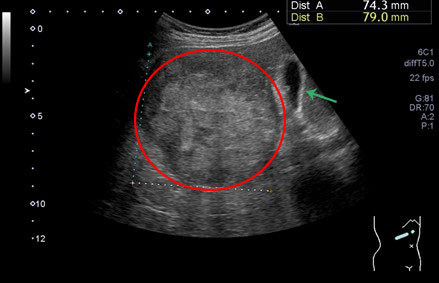

肝細胞癌の腹部超音波画像

腫瘍の右側の緑矢印↑は胆嚢

- 画像検査:腹部超音波検査やCT、造影MRI(特にEOB-MRI)は、小さな肝癌の早期発見に有用です。